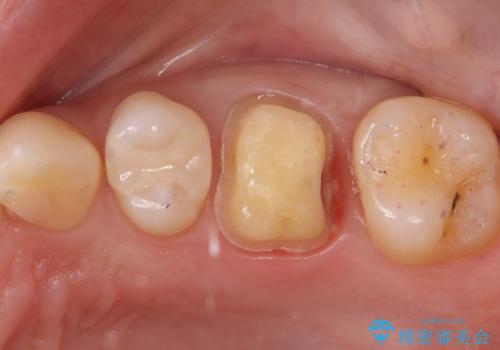

治療では、まず虫歯に侵された歯質を丁寧に除去し、セラミッククラウンを装着するための歯の形成を行いました。型取りから患者様の歯の形や色に合わせたオーダーメイドのセラミッククラウンを作製。セラミックは、隣接する歯との隙間なく精密に適合し、プラークが付着しにくいため、虫歯の再発を防ぐ効果があります。最終的に、精度の高いクラウンを装着し、咬み合わせを細かく調整しました。これにより、虫歯の再発を防ぎ、快適に食事ができる奥歯を取り戻していただけました。